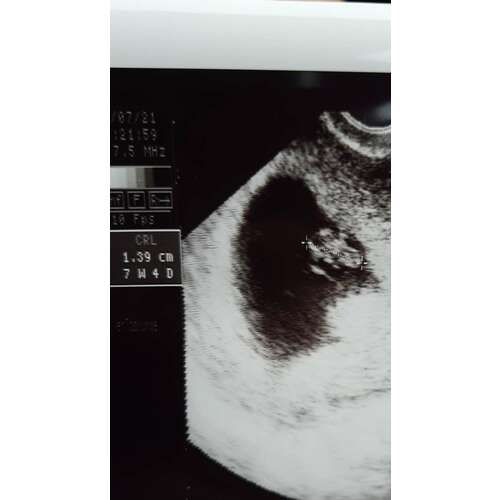

Inwendige echo bij 7w6d